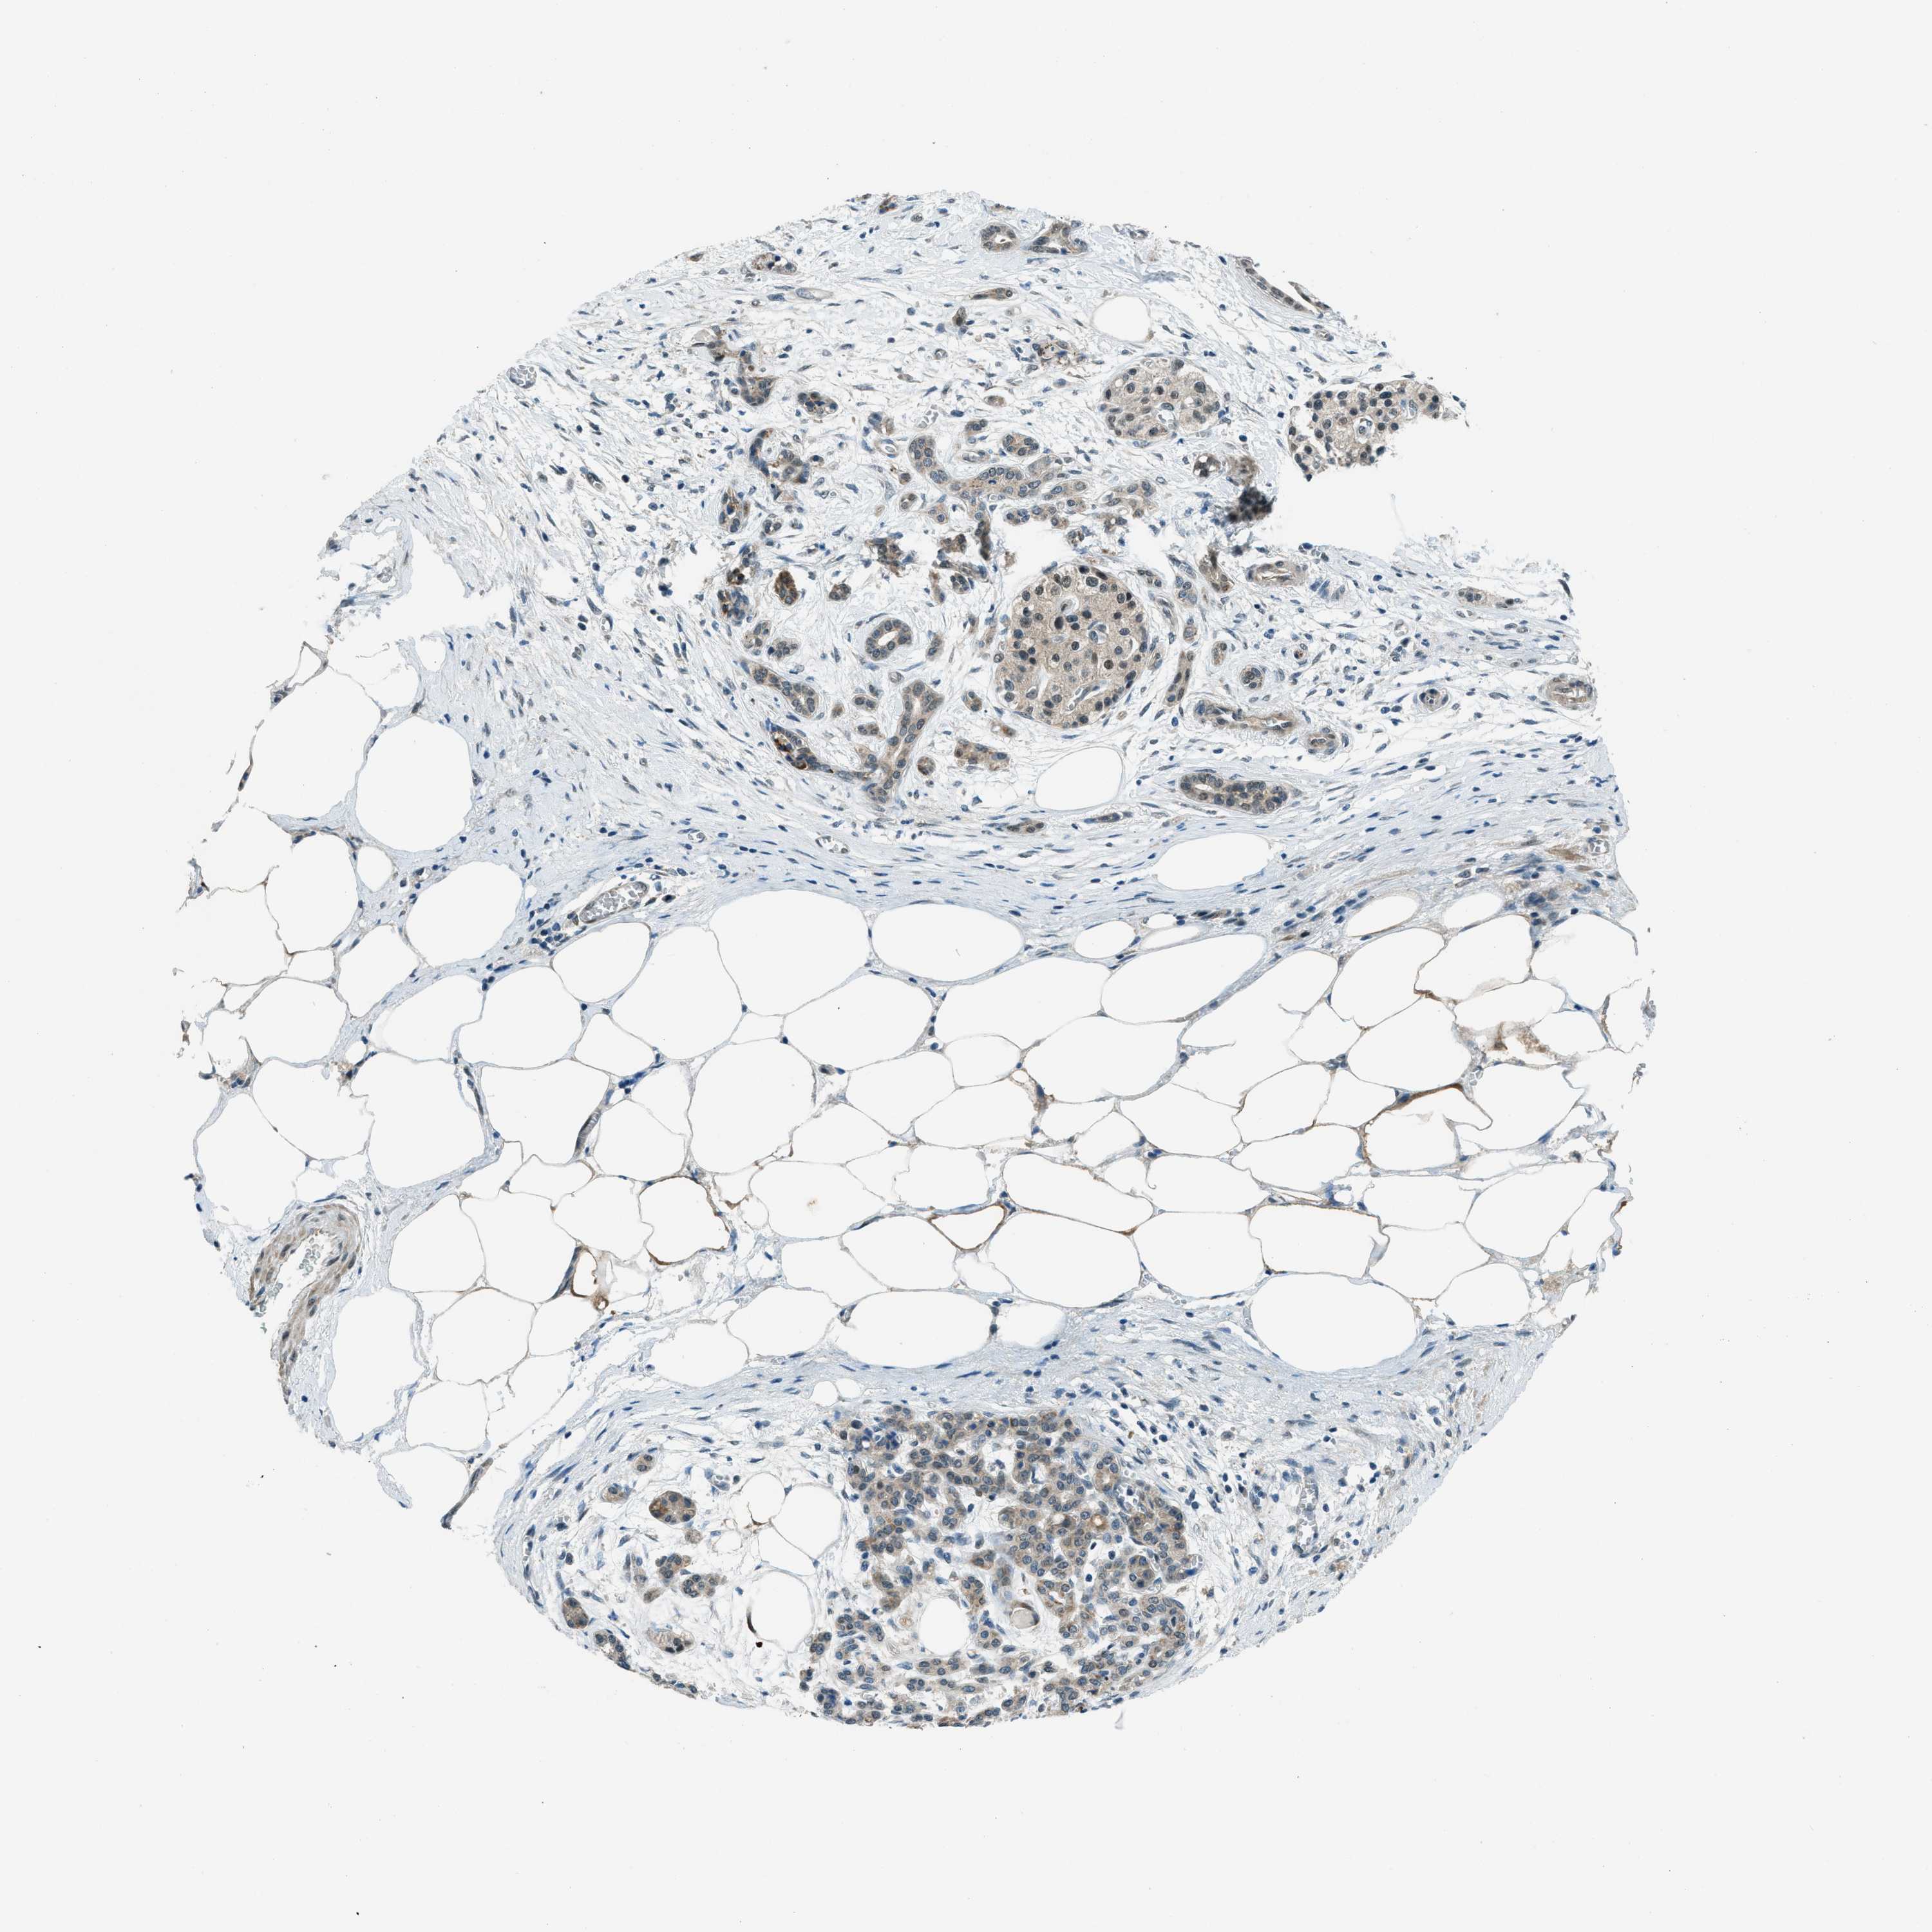

PANCREATIC CANCER - Protein expressioni

A mouse-over function shows sample information and annotation data. Click on an image to view it in a full screen mode. Samples can be filtered based on level of antibody staining by selecting one or several of the following categories: high, medium, low and not detected. The assay and annotation is described here.

Note that samples used for immunohistochemistry by the Human Protein Atlas do not correspond to samples in the TCGA dataset.

Antibody stainingi

Antibody staining in the annotated cell types in the current human tissue is reported as not detected, low, medium, or high, based on conventional immunohistochemistry profiling in selected tissues. This score is based on the combination of the staining intensity and fraction of stained cells.

Each image is clickable and will lead to virtual microscopy that enables deeper exploration of all samples and also displays staining intensity scores, fraction scores and subcellular localization as well as patient and tissue information for each sample.

Antibody HPA036356

Antibody CAB004986

Antibody CAB017025

Adenocarcinoma, NOS

Adenocarcinoma, metastatic, NOS